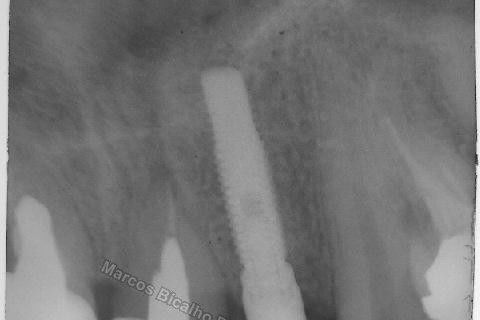

Este caso tem o objetivo de demonstração da técnica que normalmente sigo ; em casos onde ocorre fratura da raiz e consequentemente abscessos, com ou sem formação de fístula. Neste caso fiz a exodontia com preenchimento do alvéolo com biomaterial (osso bovino liofilizado + coágulo do paciente). Após 90 dias, mais ou menos, instalei o implante. Esperei mais 4 meses e realizei ontem (12/11/2010) a instalação do cicatrizador com o cuidado de preservar tecido mole, sem remoção de material, apenas afastando gengiva e "enrolando" a sobra de mucosa em direção a face vestibular, para promover conservação de papila futuramente. Se ocorrer excesso de papila, sem problema, remove-se um pouco, mas a intenção é não deixar faltar, o que resultaria em indicação para enxertos gengivais.